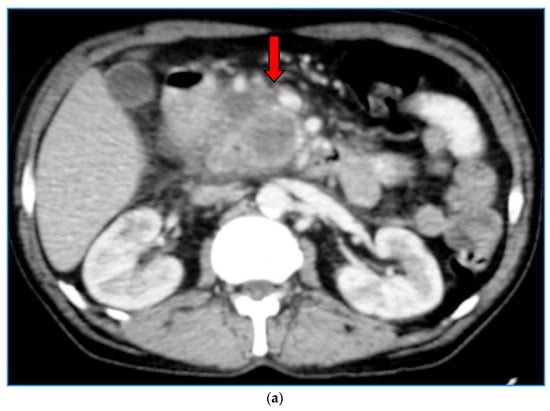

2. Imaging Findings